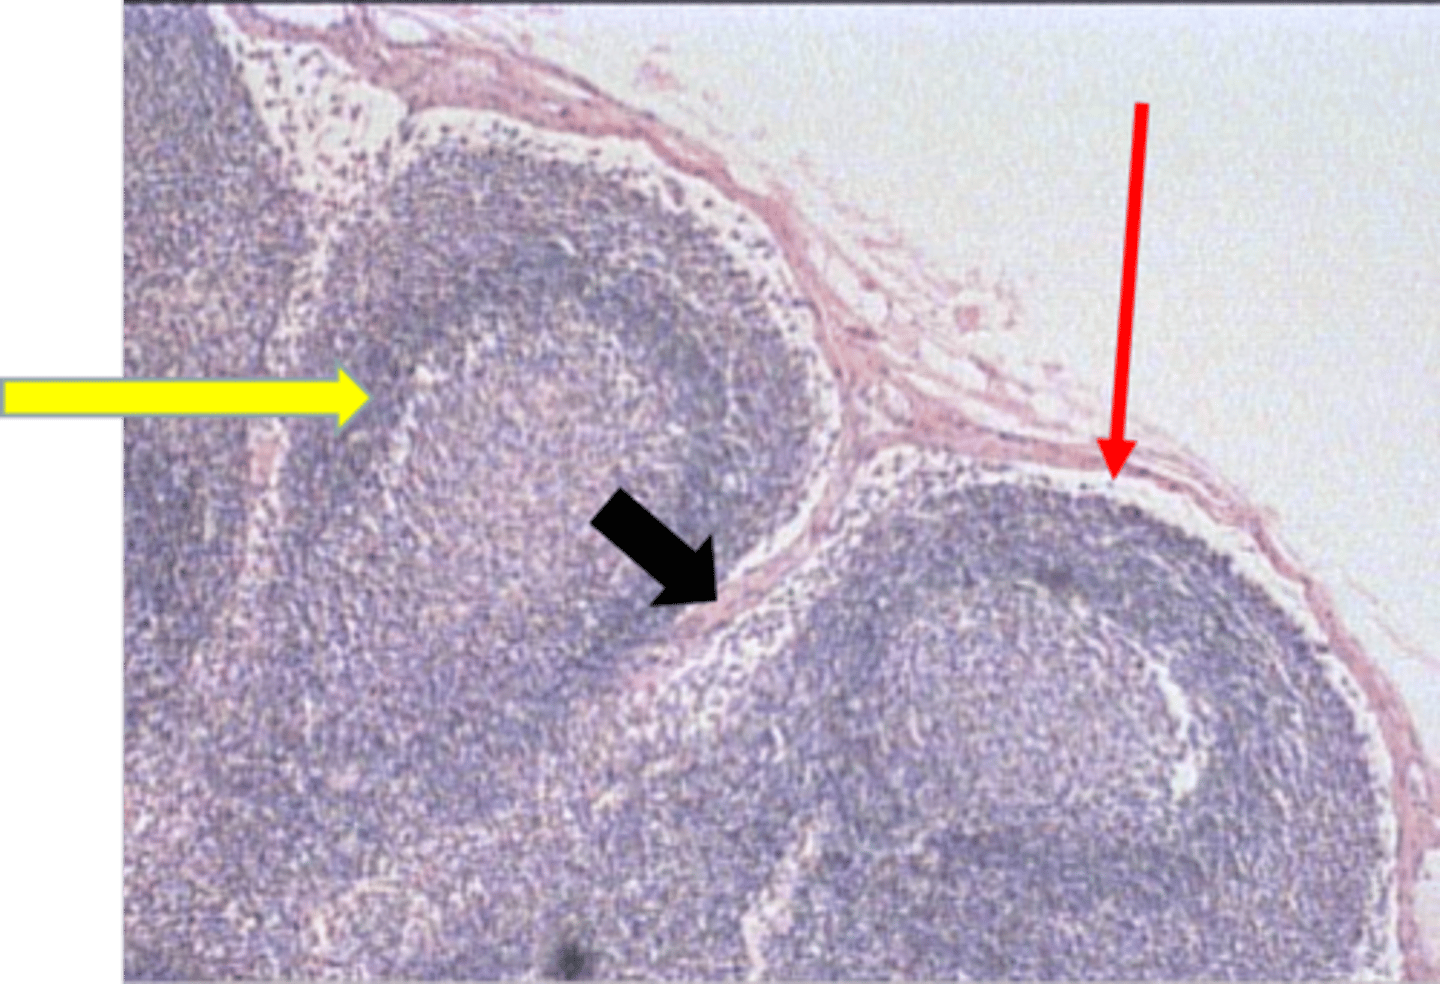

trabecula

black arrow

lymph node capsule

ID Structure

peritrabecular sinus

subcapsular sinus

secondary lymphatic nodule

red arrow

cortex of lymph node

tissue type

cortex of lymph

yellow arrow

trabeculae

subscapular sinus